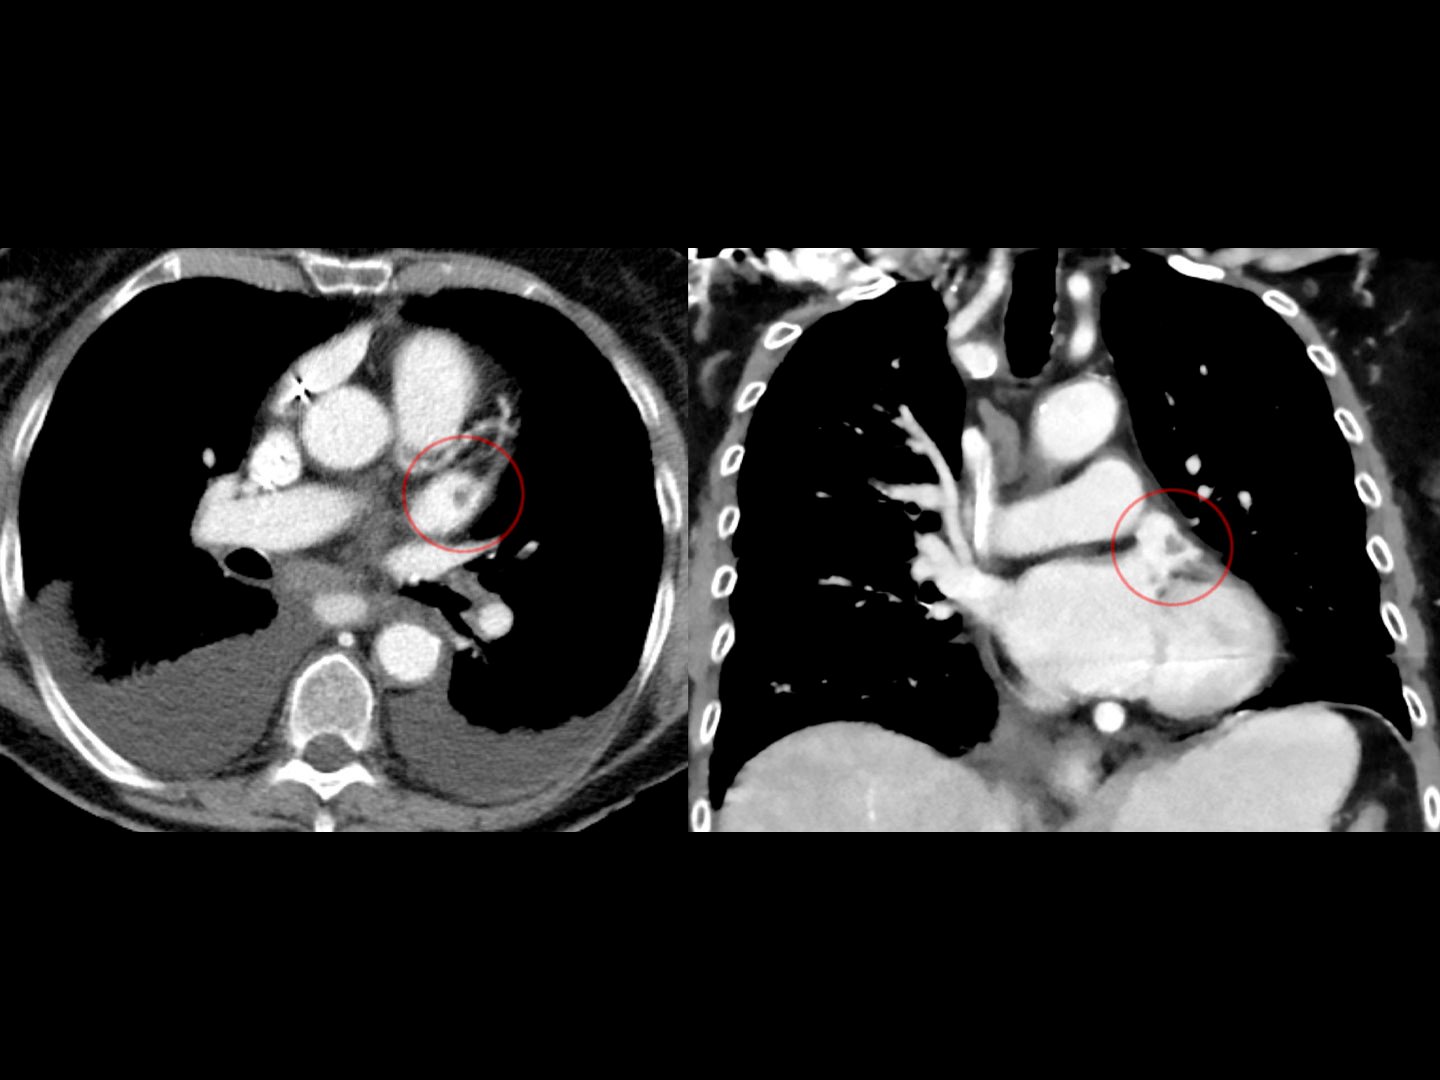

Auch im CT mit Kontrastmittel kann ein Thrombus als Aussparung des Kontrastmittels gesehen werden.

Quelle: CC BY-SA 3.0 "Zufallsbefund eines Thrombus im linken Herzohr bei einer 92-jährigen in der Computertomographie. Links axial, rechts koronar.". Wikimedia Commons. User: Hellerhoff

CT Vorhofthrombus - Auch im CT mit Kontrastmittel kann ein Thrombus als Aussparung des Kontrastmittels gesehen werden.

Prinzipiell kann eine echokardiographische Untersuchung transthorakal erfolgen (TTE) oder transösophageal (TEE). Zum Ausschluss von Thromben z.B. vor einer Kardioversion ist eine TEE Abb. 852 zu empfehlen. Prinzipiell kann ein Thrombus auch im CT mit KM Abb. 853 gesehen werden.

Prinzipiell kann eine echokardiographische Untersuchung transthorakal erfolgen (TTE) oder transösophageal (TEE). Zum Ausschluss von Thromben z.B. vor einer Kardioversion ist eine TEE [[Abb. 8522]] zu empfehlen. Prinzipiell kann ein Thrombus auch im CT mit KM [[Abb. 8533]] gesehen werden.